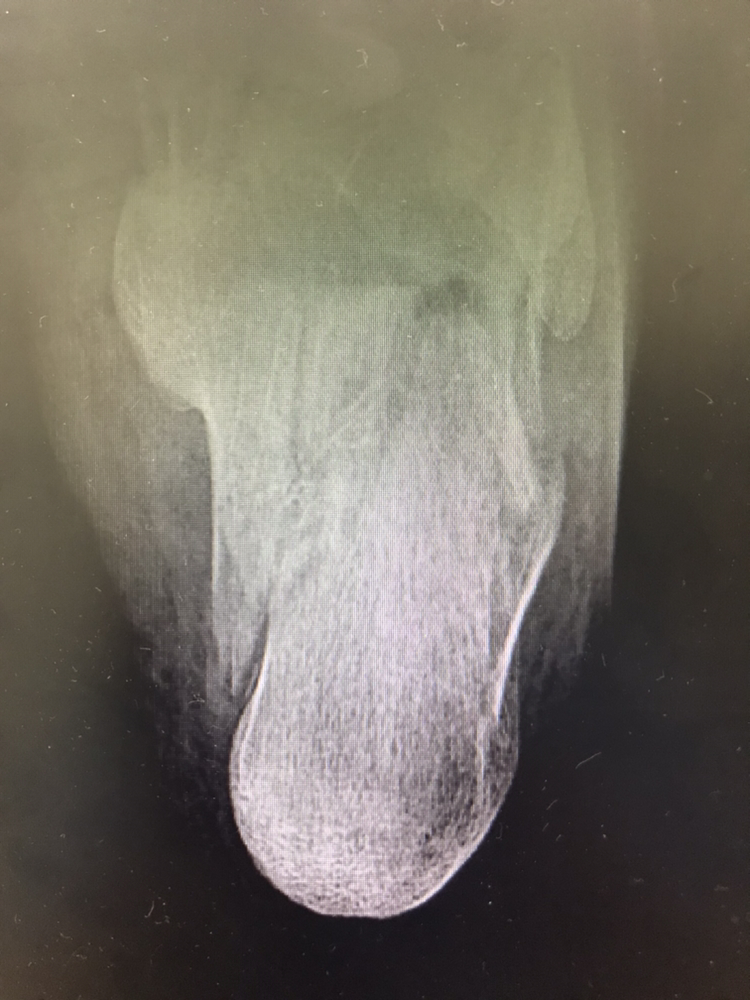

머리 부딪혀 뇌출혈,

다리 꺾여서 골절이

돌연 생기곤 합니다.